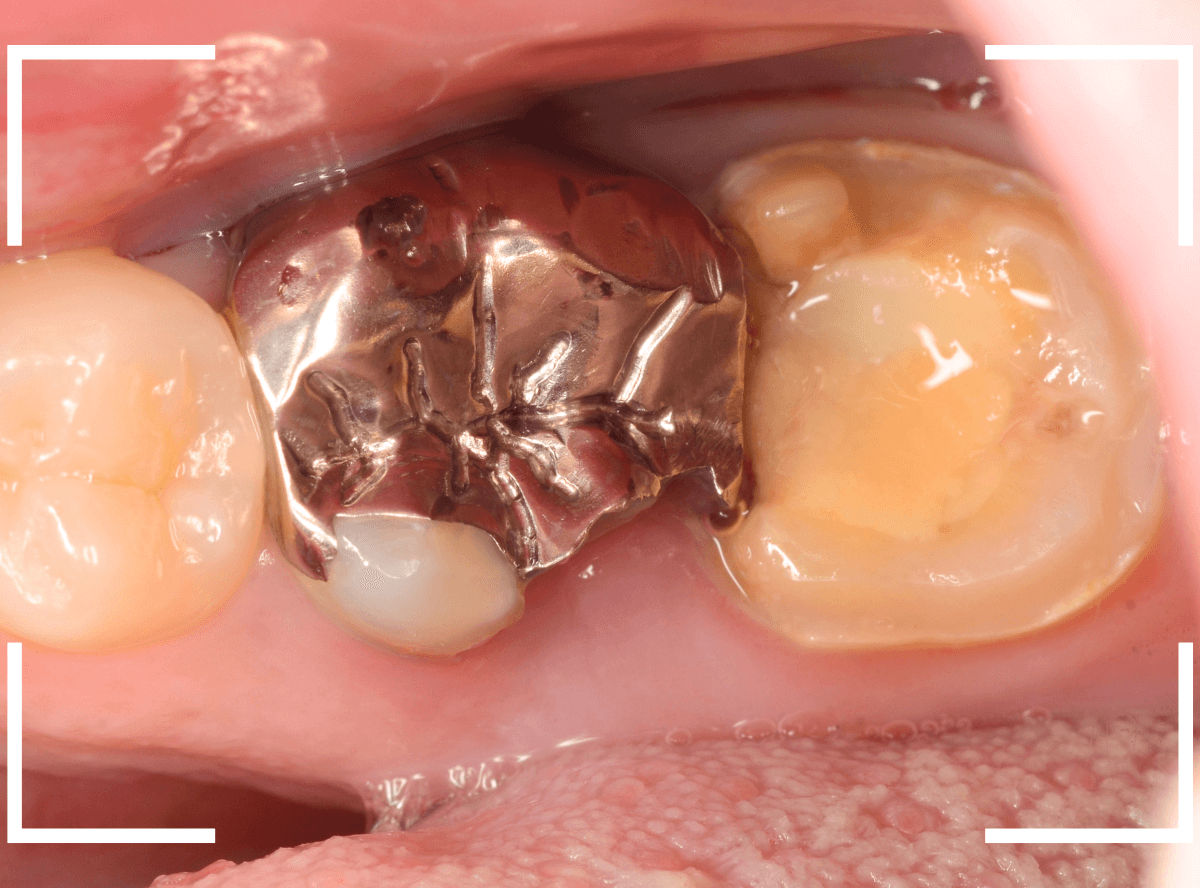

Case.15 歯肉の中まで、虫歯が進行

今回は、下の奥歯が虫歯になってしまった方です。

銀歯の下が大きくかけていますが、神経を取っている歯なので痛みはありません。

隣りの奥歯は、土台のまま治療途中になっています。

レントゲン写真で確認します。

赤い部分が虫歯、青い線が歯肉のラインです。

奥歯2本とも虫歯になっています。

どちらも虫歯が深く、歯肉の中まで入り込んでいると思われます。

この虫歯の深さは、最悪、抜歯が必要になるかもしれないケースです。

神経のない歯ですが、歯肉を処置する必要があるため、麻酔をして治療します。

まず、つめものを外します。

歯肉を処置しながら、虫歯を除去します。

虫歯の全て除去後、止血したところです。

かなり深いところまで虫歯が進行していましたが、なんとかぎりぎり抜歯せずに、土台を作って噛み合わせを回復できそうです。